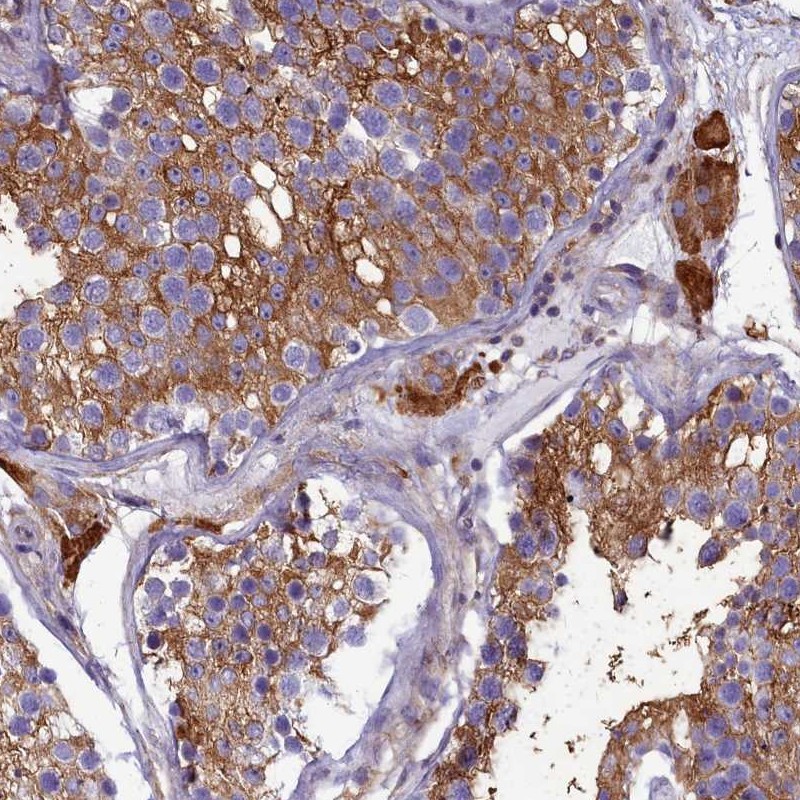

Immunohistochemical staining of human testis shows strong cytoplasmic positivity in cells in seminiferus ducts and Leydig cells.